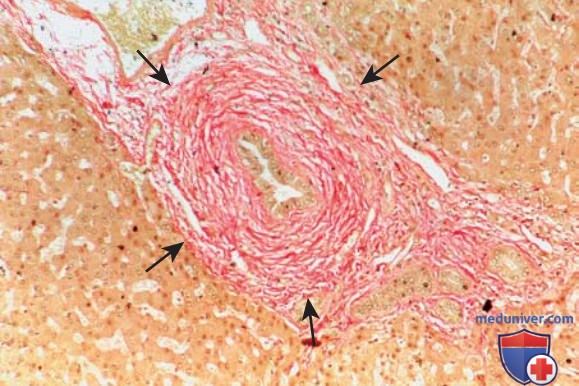

Фотографии и изображения, связанные с симптомами первичного склерозирующего холангита